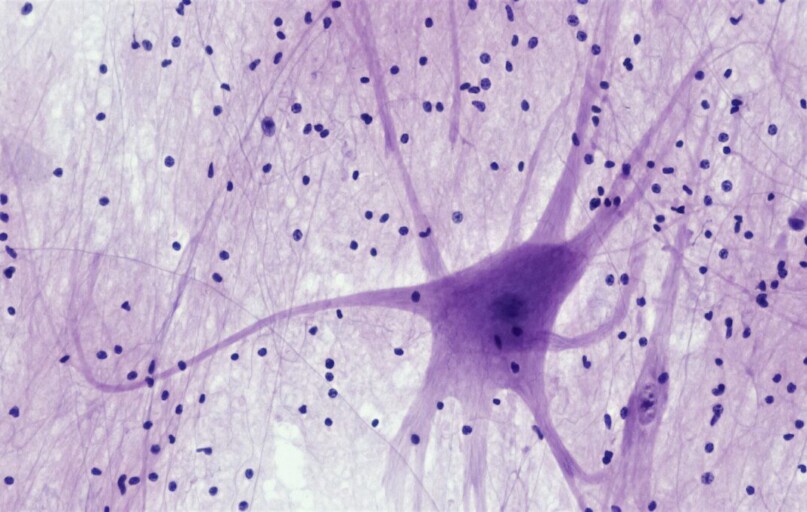

Smegenys sensta kartu su visu organizmu. Bėgant metams jos pagamina vis mažiau naujų nervinių ląstelių, tačiau mokslininkams pavyko nustatyti svarbų mechanizmą, kuris galėtų sulėtinti įprastą, su amžiumi susijusį neuronų gamybos mažėjimą.

Vėlesniame gyvenimo etape nervų kamieninės ląstelės (NSC), iš kurių formuojasi visiškai subrendę neuronai, tampa vis pasyvesnės – tarsi po ilgo darbo „išeitų į pensiją“. Silpstant šių ląstelių aktyvumui, palaipsniui ryškėja ir pažintinių funkcijų prastėjimas: silpnėja atmintis, mokymosi gebėjimai, dėmesio koncentracija.

Derindami žmogaus nervų kamieninių ląstelių tyrimus laboratorijoje ir bandymus su pelėmis, mokslininkai išskyrė vieną reikšmingą baltymą – ciklino D prisijungiantį myb tipo transkripcijos faktorių 1 (DMTF1). Transkripcijos faktoriai prisijungia prie DNR ir įjungia arba išjungia konkrečius genus, taip reguliuodami ląstelės veiklą.